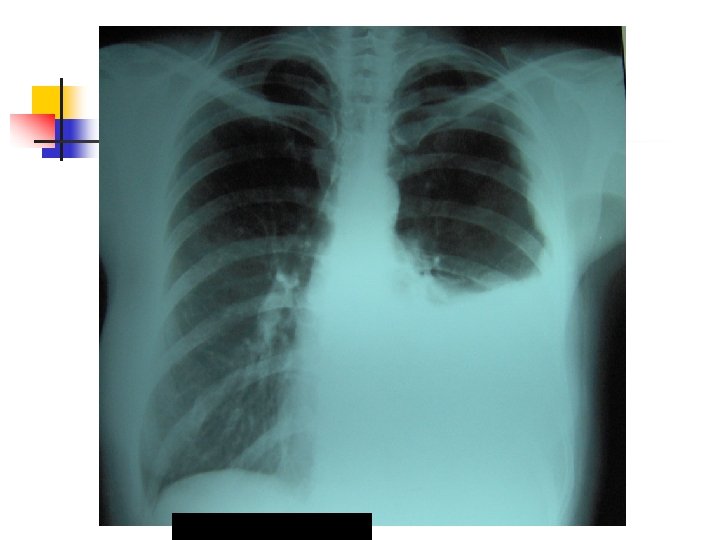

Aproximación diagnóstica: Radiología n n n 250 ml son necesarios para provocar alteraciones radiológicas. Primer signo: Borramiento del SCD Damoisseau. Desviación de estructuras. Derrame tabicado.